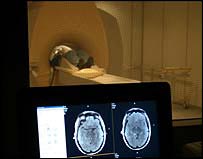

Os homens parecem sentir mais satisfação do que as mulheres ao testemunhar a punição de alguém que agiu de forma considerada injusta, segundo pesquisa feita na Grã-Bretanha. Cientistas da University College London monitoraram a atividade cerebral de um grupo de voluntários enquanto estes observavam pessoas de quem gostavam e não gostavam sendo fisicamente castigadas. Enquanto as mulheres pareciam sentir empatia por todos os punidos, os homens mostravam sinais de prazer ao ver seus inimigos sentindo (ou aparentando sentir) dor. O estudo foi publicado na revista Nature. Honestos e desonestos Participaram da pesquisa 32 voluntários, homens e mulheres, e ainda quatro atores que tiveram suas identidades mantidas em segredo. Na primeira fase do estudo, os participantes jogaram um jogo de tabuleiro. Durante o jogo, alguns dos atores se projetaram como pessoas boazinhas, jogando honestamente, enquanto outros jogaram sujo, despertando a antipatia dos voluntários. Na fase seguinte, os atores simularam receber choques elétricos enquanto os voluntários tinham sua atividade cerebral monitorada. Quando os atores "honestos" receberam choques, homens e mulheres apresentaram aumento da atividade cerebral nas regiões do cérebro associadas à dor. Quando o ator "desonesto" recebeu um choque, as mulheres apresentaram respostas semelhantes de empatia. Os homens, porém, não mostraram sinais de empatia ao ver o ator "desonesto" sendo castigado. Pelo contrário, os voluntários do sexo masculino apresentaram aumento de atividade na região do cérebro associada ao prazer. Os pesquisadores observaram que os voluntários tendiam a evitar as pessoas que tinham agido de forma desonesta, e sua antipatia foi confirmada em um questionário. A cientista responsável pelo estudo, Tania Singer, disse que os Mas ela acrescentou que é possível que os homens tenham reagido dessa forma porque o tipo de punição foi físico, e não psicológico ou financeiro. Comentando o estudo, o neuropsicólogo Colin Wilson, do Instituto de Saúde Green Park, em Belfast, disse que para se saber ao certo se existem de fato diferenças profundas entre homens e mulheres quando se trata de punição e vingança, seriam necessárias mais pesquisas. Wilson disse que é possível que as mulheres tendam a refletir mais, e estejam menos inclinadas a fazer julgamentos rápidos e de natureza punitiva. Para o pesquisador, seria interessante observar o comportamento dos voluntários em relação a outros tipos de castigo, como, por exemplo, um insulto ou uma repreensão. |